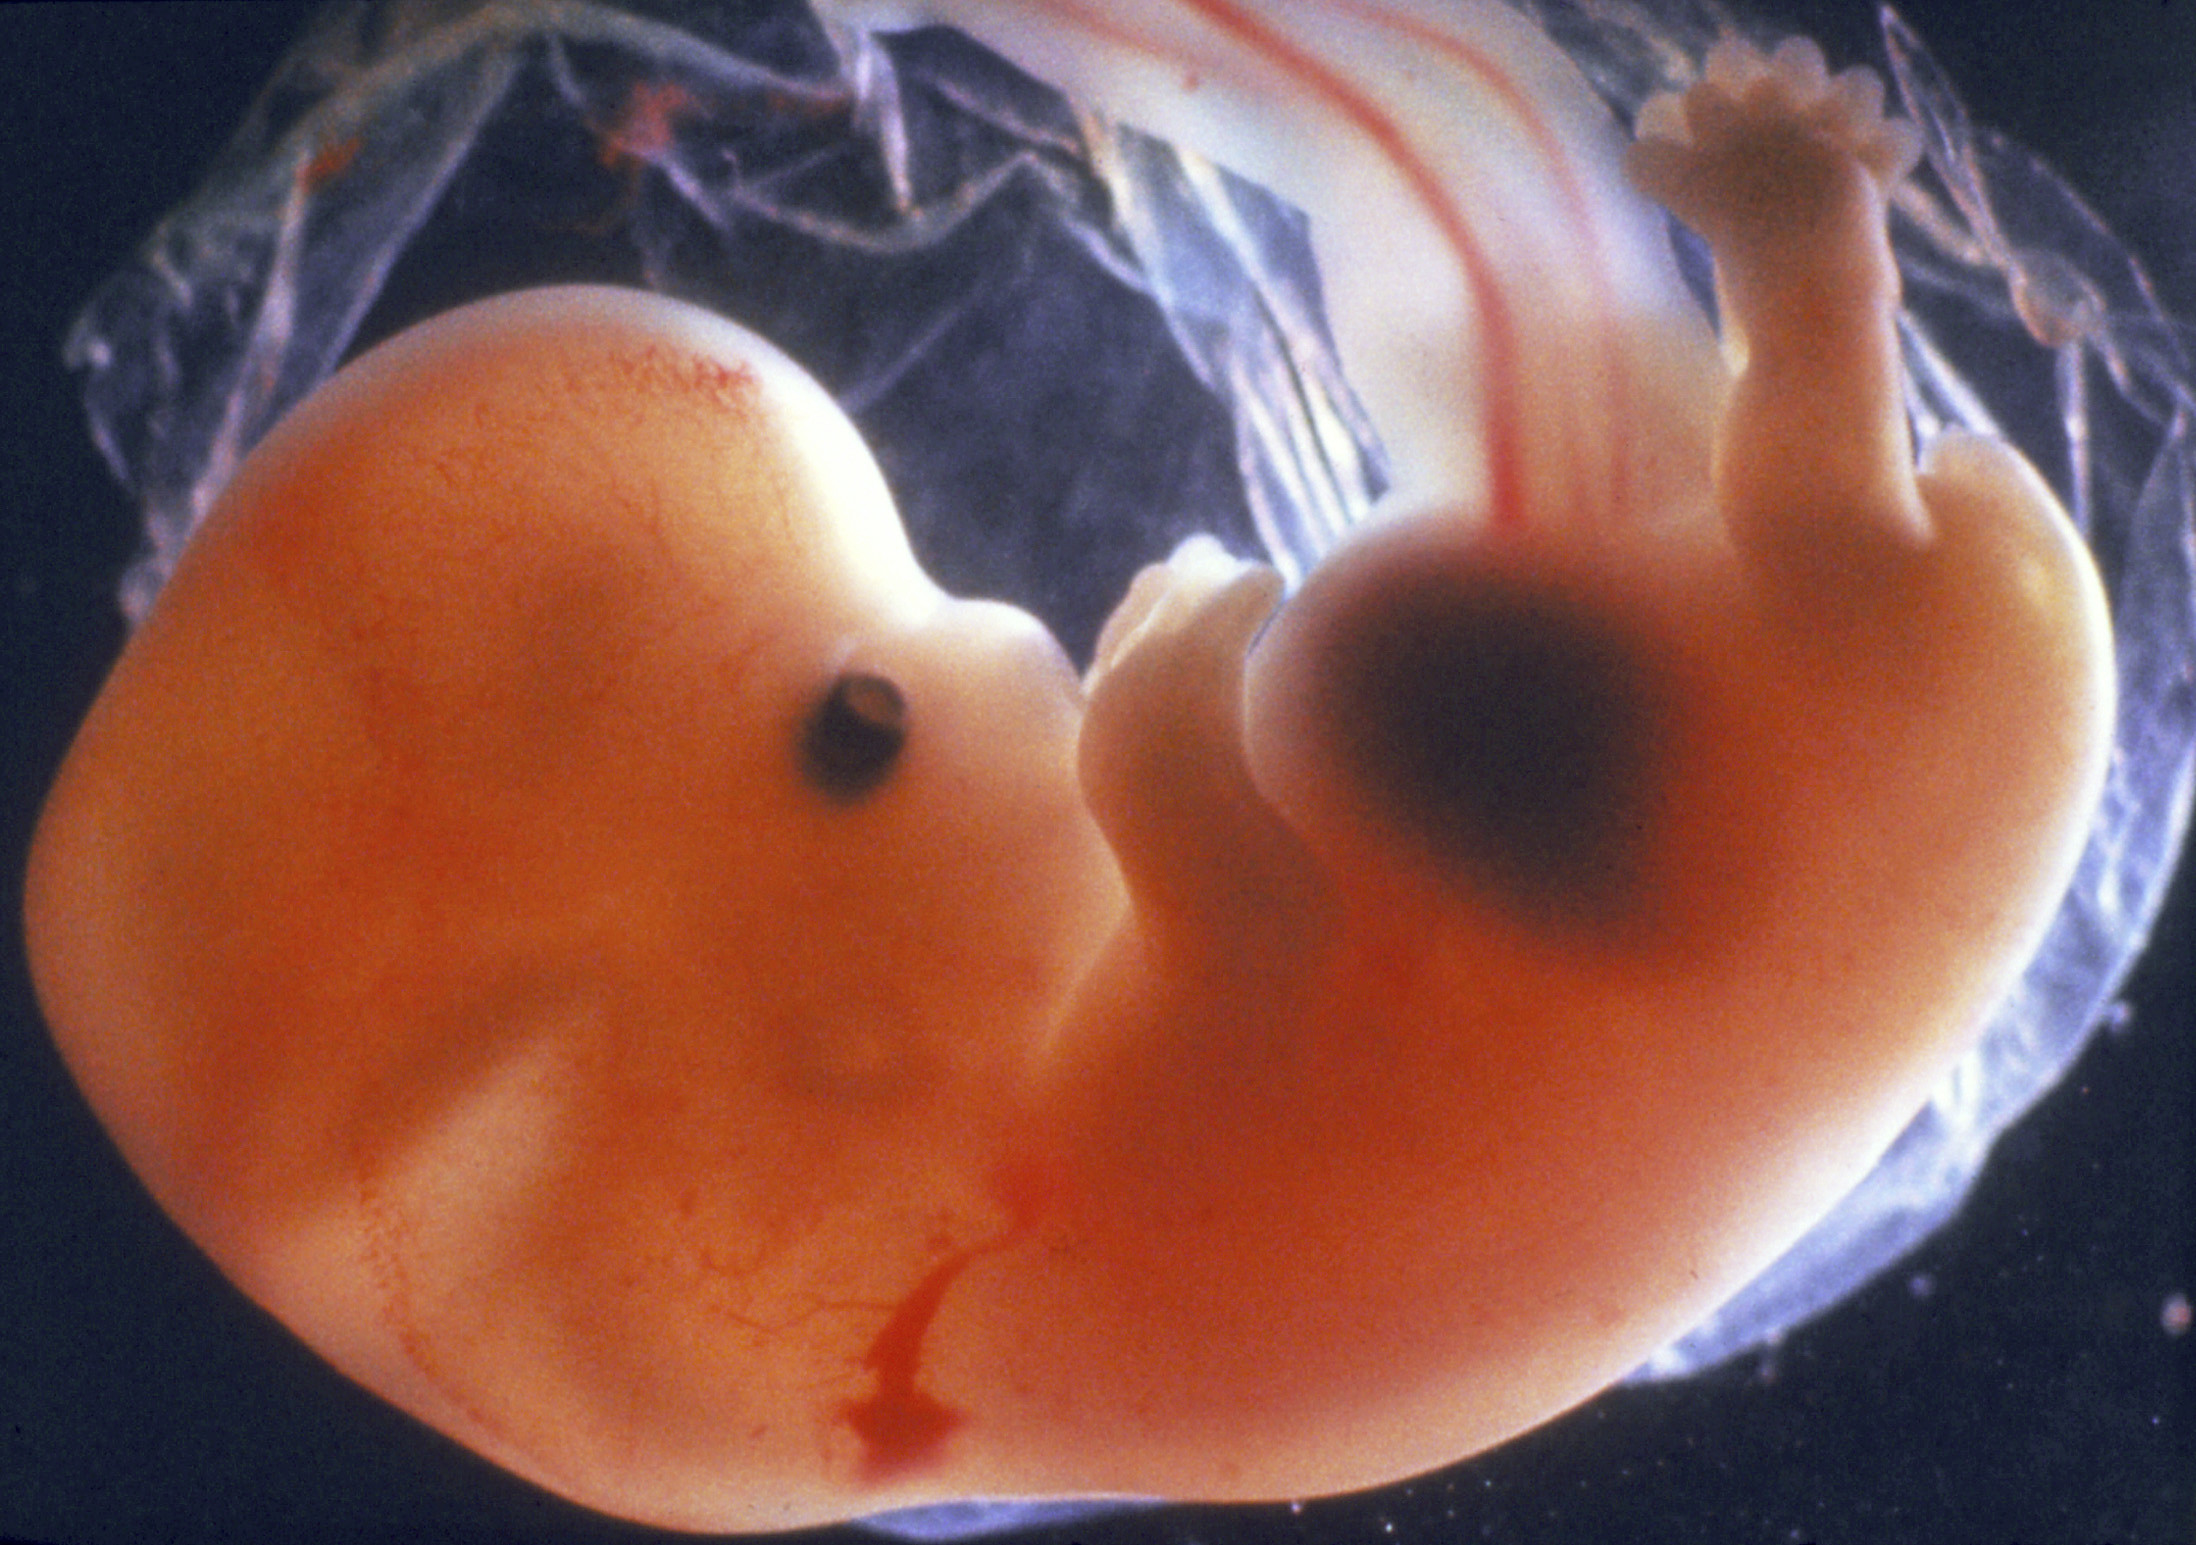

Удивительные фотографии эмбриона на 8 неделе беременности